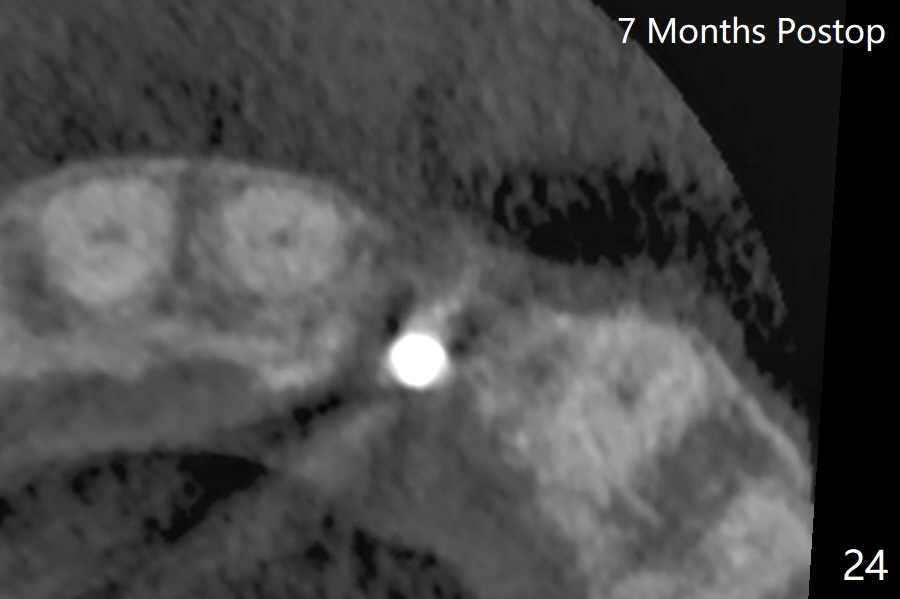

病人回来带来瘘道(图一),不过不会增加难度,病牙去除,它便自动消失。尽管颊侧骨壁完全失去,颊侧牙龈仍丰满(图二),为什么呢?第一,因为粗大牙根存在,第二两旁牙齿,牙槽骨撑着帐篷(侧切牙颊侧牙龈),第三,牙冠。为了防止术后牙龈塌陷,尽量不切开,即刻放置植体(牙根);由于前牙缘故,这次植体不能很大,所以植骨必须过度(over grafting),最后即刻制作临时牙冠,撑住牙龈。这就是所谓每个人进入角色。这个牙根有一种先天性畸形:dens in dent (图三(腭侧观):箭头)。尽管腭侧牙根畸形,腭侧骨壁吸收临床上并不严重,所以钻洞仍偏腭侧。当预定最后钻头还在钻洞时,填入大量粘性骨块(图四:*),细长植体还没有完全卡入鼻底(图五),最后好像可以(图六,七)。植体,骨粉入位(图八),最后临时牙冠出场(图九)。尽管植体小,术后一周临时牙冠仍然可以维持牙龈原有形状(emergency profile,图十:箭头(*:树脂强化牙冠固定))。图十一以不同角度显示瘘道缩小。术后三周取出有些松动的临时牙冠,骨粉虽然还没有被肉芽组织整合,但是显得正常,周围牙龈健康(图十二)。术后4个月牙龈形态正常(图十三),没有触痛;颊侧骨板轻度凹陷(图十四);骨粉仍在原位(图十五)。术后7个月骨粉仍在原位(图十五,十六,但是冠部密度减低(可能骨粉流失,需要牙周或者树脂敷料保护)),没有螺纹暴露。但是牙冠边缘暴露,说明牙龈收缩(图十七,与图十三对比),颊侧骨板仍塌陷(图十八)。插入龈线取得多个目的:修整基台边缘,取模,颊侧牙龈推向颊侧,有利于即将衬里牙冠龈缘进入龈下(图十九)。取模后牙冠边缘(图二十:<)衬里,然后修整,变窄,以便插入龈下,促进颊侧牙龈下降(图二十一,二十二)。术后8个月牙冠粘固前牙龈健康(图二十七,八),牙冠(图二十九)固位后,病人满意(图三十),咬合调整(图三十一),注意腭侧粘固粉流出通道(<)。